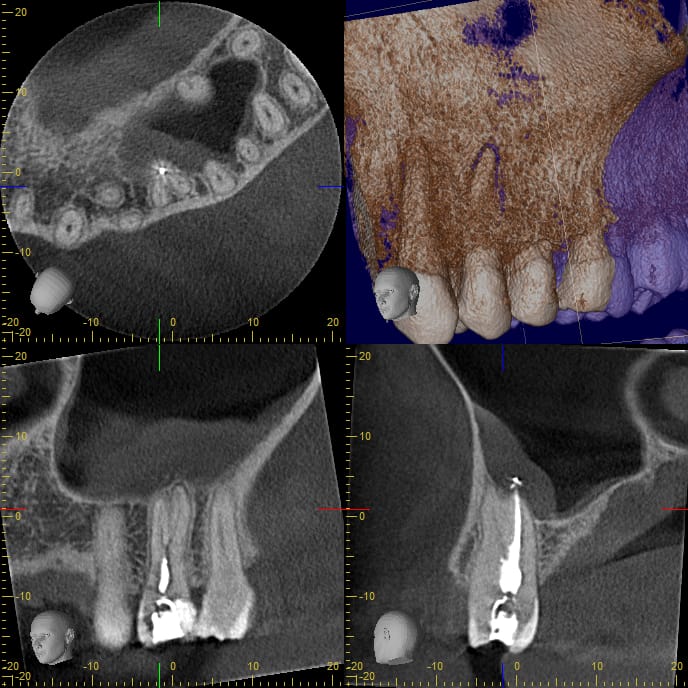

Tendințe moderne în diagnosticul și tratamentul afecțiunilor endodontice

Conf. Univ. Dr Oana Diaconu, Sef Lucr.Dr. Gheorghita Lelia, Asist. Univ. Anca Gheorghe, Drd. Aurelian Carstea, Drd. Cezar Diaconu, Prof.Univ. Dr. Tuculina Mihaela*

Noi direcții de diagnostic și tratament în leziunile endo-parodontale

Prof. Univ. Dr. M. J. Ţuculină, Conf. Univ. Dr. O. A. Diaconu, Ș.L. Dr. I. Moraru, Ș.L. Dr. L. M. Gheorghiță, Prof. Univ. Dr. A. Iliescu